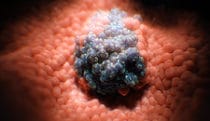

Malignant Cell

Work -